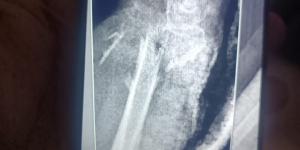

مستشفى الفيوم العام تنقذ حياة سيدة مسنّة بعد سقوط من علو وتجري جراحة ميكروسكوبية دقيقة باليدمصرمنذ 3 أشهر